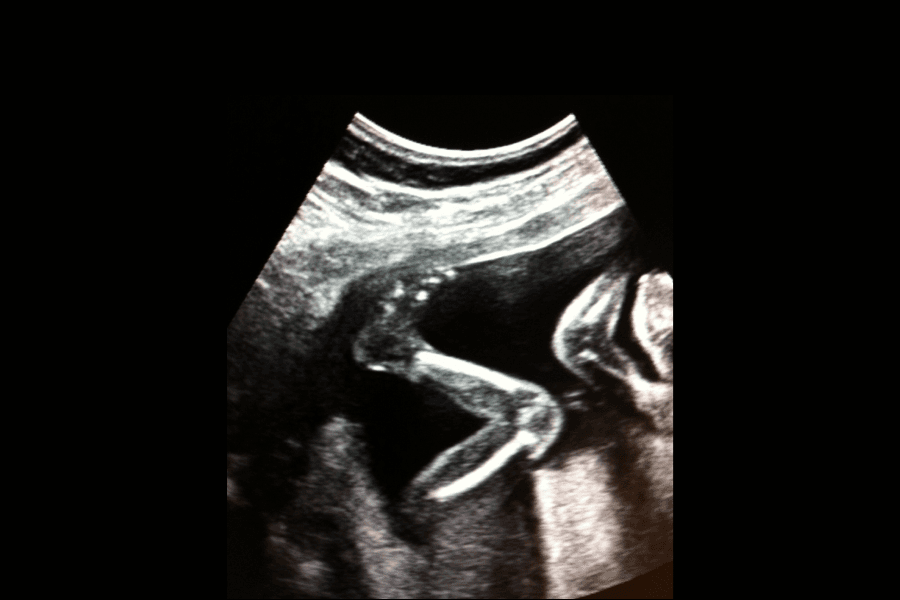

Mot slutten av svangerskapet kan man ofte kjenne at babyen har perioder hvor den er våken, og ikke sjelden tilsvarer disse periodene med hvordan babyen vil være våken eller sove etter fødselen. Under svangerskapet er våkne perioder preget av mye bevegelse og ofte er disse våkne periodene på ettermiddagen eller kvelden. Det er ingen bevis for at babyen beveger seg mindre på slutten av svangerskapet, men opplevelsen av bevegelsene kan føles annerledes sammenlignet med tidligere. Mange beskriver bevegelsene på slutten av svangerskapet som mer trykkende, nesten som vendinger.